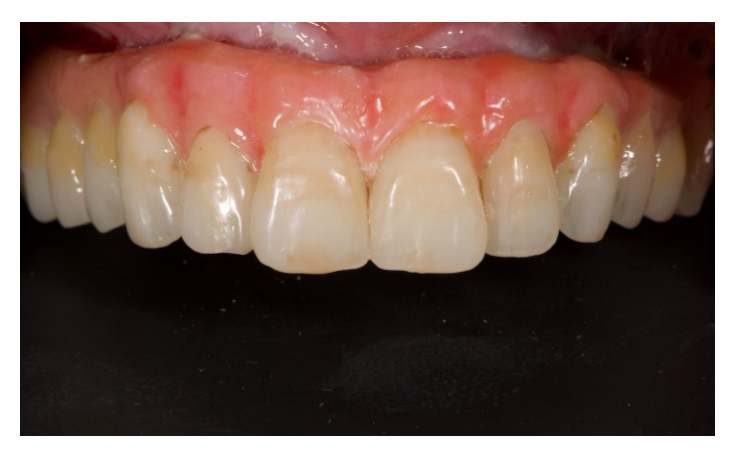

После этого эстетическая примерка была снята. Четыре новые скан-аналоги были подключены к временным абатментам и отсканированы вне рта пациента с помощью обычного экстраорального сканера (Рисунок 21). Прежде чем была изготовлена окончательная CAD/CAM конструкция, клинически и радиографически была протестирована радиопрозрачная алюминиевая конструкция. После этого было выполнено перекрестное монтаж окончательной реставрации (позиция имплантата) с функционализированной временной реставрацией, а также с оригинальным планом. На следующем приеме титановая CAD/CAM конструкция была протестирована в рту пациента. В конце концов, была доставлена фиксированная, удерживаемая винтом, имплантоподдерживаемая реставрация, изготовленная из титана, с композитом в качестве облицовочного материала (Рисунки 22–24). Композит был выбран из-за своей прочности и способности к поглощению ударов. Лингвализированный окклюзия была спроектирована для всех окончательных реставраций, с использованием анатомических зубов для верхнего протеза и модифицированных неанатомических или полуанатомических зубов для нижних протезов.

Второй инновацией стало представление протезно-ориентированного имплантационного лотка, предназначенного для записи точного цифрового отпечатка для восстановления полного зубного ряда. Талларико и его коллеги в 2017 и 2018 годах представили несколько клинических случаев, демонстрирующих один и тот же протезный шаблон. Спустя несколько лет тот же автор опубликовал in vitro исследование, которое показало, что протезно-ориентированный шаблон для отпечатков значительно улучшает точность и прецизионность полного беззубого зубного ряда, восстановленного с помощью четырех или шести имплантов, делая цифровой отпечаток полного зубного ряда более предсказуемым. Похожие результаты были получены в нескольких клинических случаях Венецией и соавторами. Этот подход не только позволяет передавать межчелюстные и окклюзионные отношения, но также улучшает общую точность цифрового отпечатка. Хорошо известно, что точность отпечатков полного зубного ряда по-прежнему является сложной задачей для устройств интраорального сканирования. С другой стороны, ограниченные клинические различия были обнаружены при сравнении цифровых и традиционных отпечатков, сделанных для восстановления имплантоподдерживаемых частичных реставраций. Для последних основной целью протезно-ориентированного имплантационного лотка является улучшение точности цифровых отпечатков полного зубного ряда, добавляя несколько контрольных точек между сканирующими абатментами. Эта концепция почти аналогична снятию частичного цифрового отпечатка. Кроме того, дизайн протезно-ориентированного имплантационного лотка был основан на временной реставрации, функционализированной в ротовой полости пациента. Поэтому может быть выполнена техника перекрестного монтажа для создания идеальной, эстетичной и функциональной копии временной реставрации. Наконец, эстетику и функцию можно протестировать на приеме, что упрощает доставку окончательной реставрации.